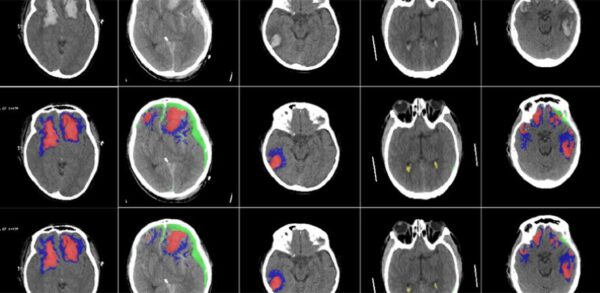

“Computertomografie is een ongelooflijk belangrijk diagnostisch hulpmiddel, maar het wordt zelden kwantitatief gebruikt”, zegt professor David Menon van het Department of Medicine binnen de universiteit. “CT-scans bevatten heel veel informatie, waarvan vaak een groot deel wordt gemist.”

Het is volgens onderzoeker Virginia Newcombe ook een kwestie van tijd. “Een gedetailleerde beoordeling van een CT-scan kan uren duren, vooral bij patiënten met ernstige verwondingen. Wij wilden een instrument ontwikkelen dat automatisch en snel de verschillende soorten hersenletsel kan identificeren en kwantificeren.”

Voor de studie ontwikkelden de onderzoekers een kunstmatig neuraal netwerk dat ze trainde met behulp van ruim 600 CT-scans waarop alle soorten van hersenletsel te zien waren in meerdere gradaties van ernstigheid. Vervolgens hebben ze het neurale netwerk weer getest met een grote dataset van CT-scans. En daar is een KI-algoritme uitgerold dat in staat is heel nauwkeurige diagnoses te stellen en te zeggen of een hersenscan normaal is of niet. “We hopen dat het ons zal helpen in de toekomst een meer gepersonaliseerde behandeling voor patiënten te ontwikkelen,” zegt Menon.